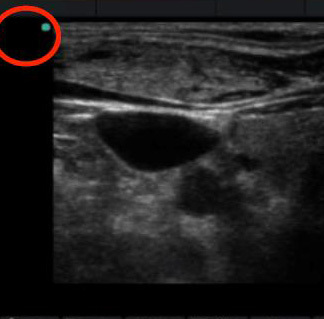

Transducer Marker Orientation Graphic